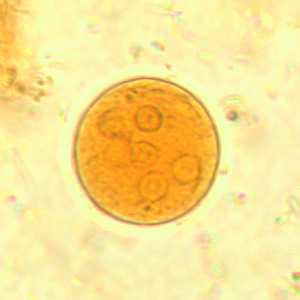

E. coli cysts in concentrated wet mounts.

Figure B: Cyst of E. coli in a concentrated wet mount stained with iodine. Five nuclei are visible in this focal plane.